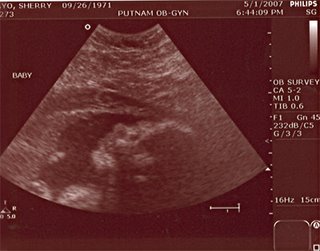

--Junior looks to be bit better than 4 lbs with a very good tummy circumference measurement -- whatever that is good for. We just don't know how long Junior is but I do know that Junior has a foot fetish and tries hard to grab for its feet, frequently -- which is obviously getting harder for Junior to accomplish -- hence all that squirming on my right-side from bottom to top. (*You'd think Junior a PISCES)